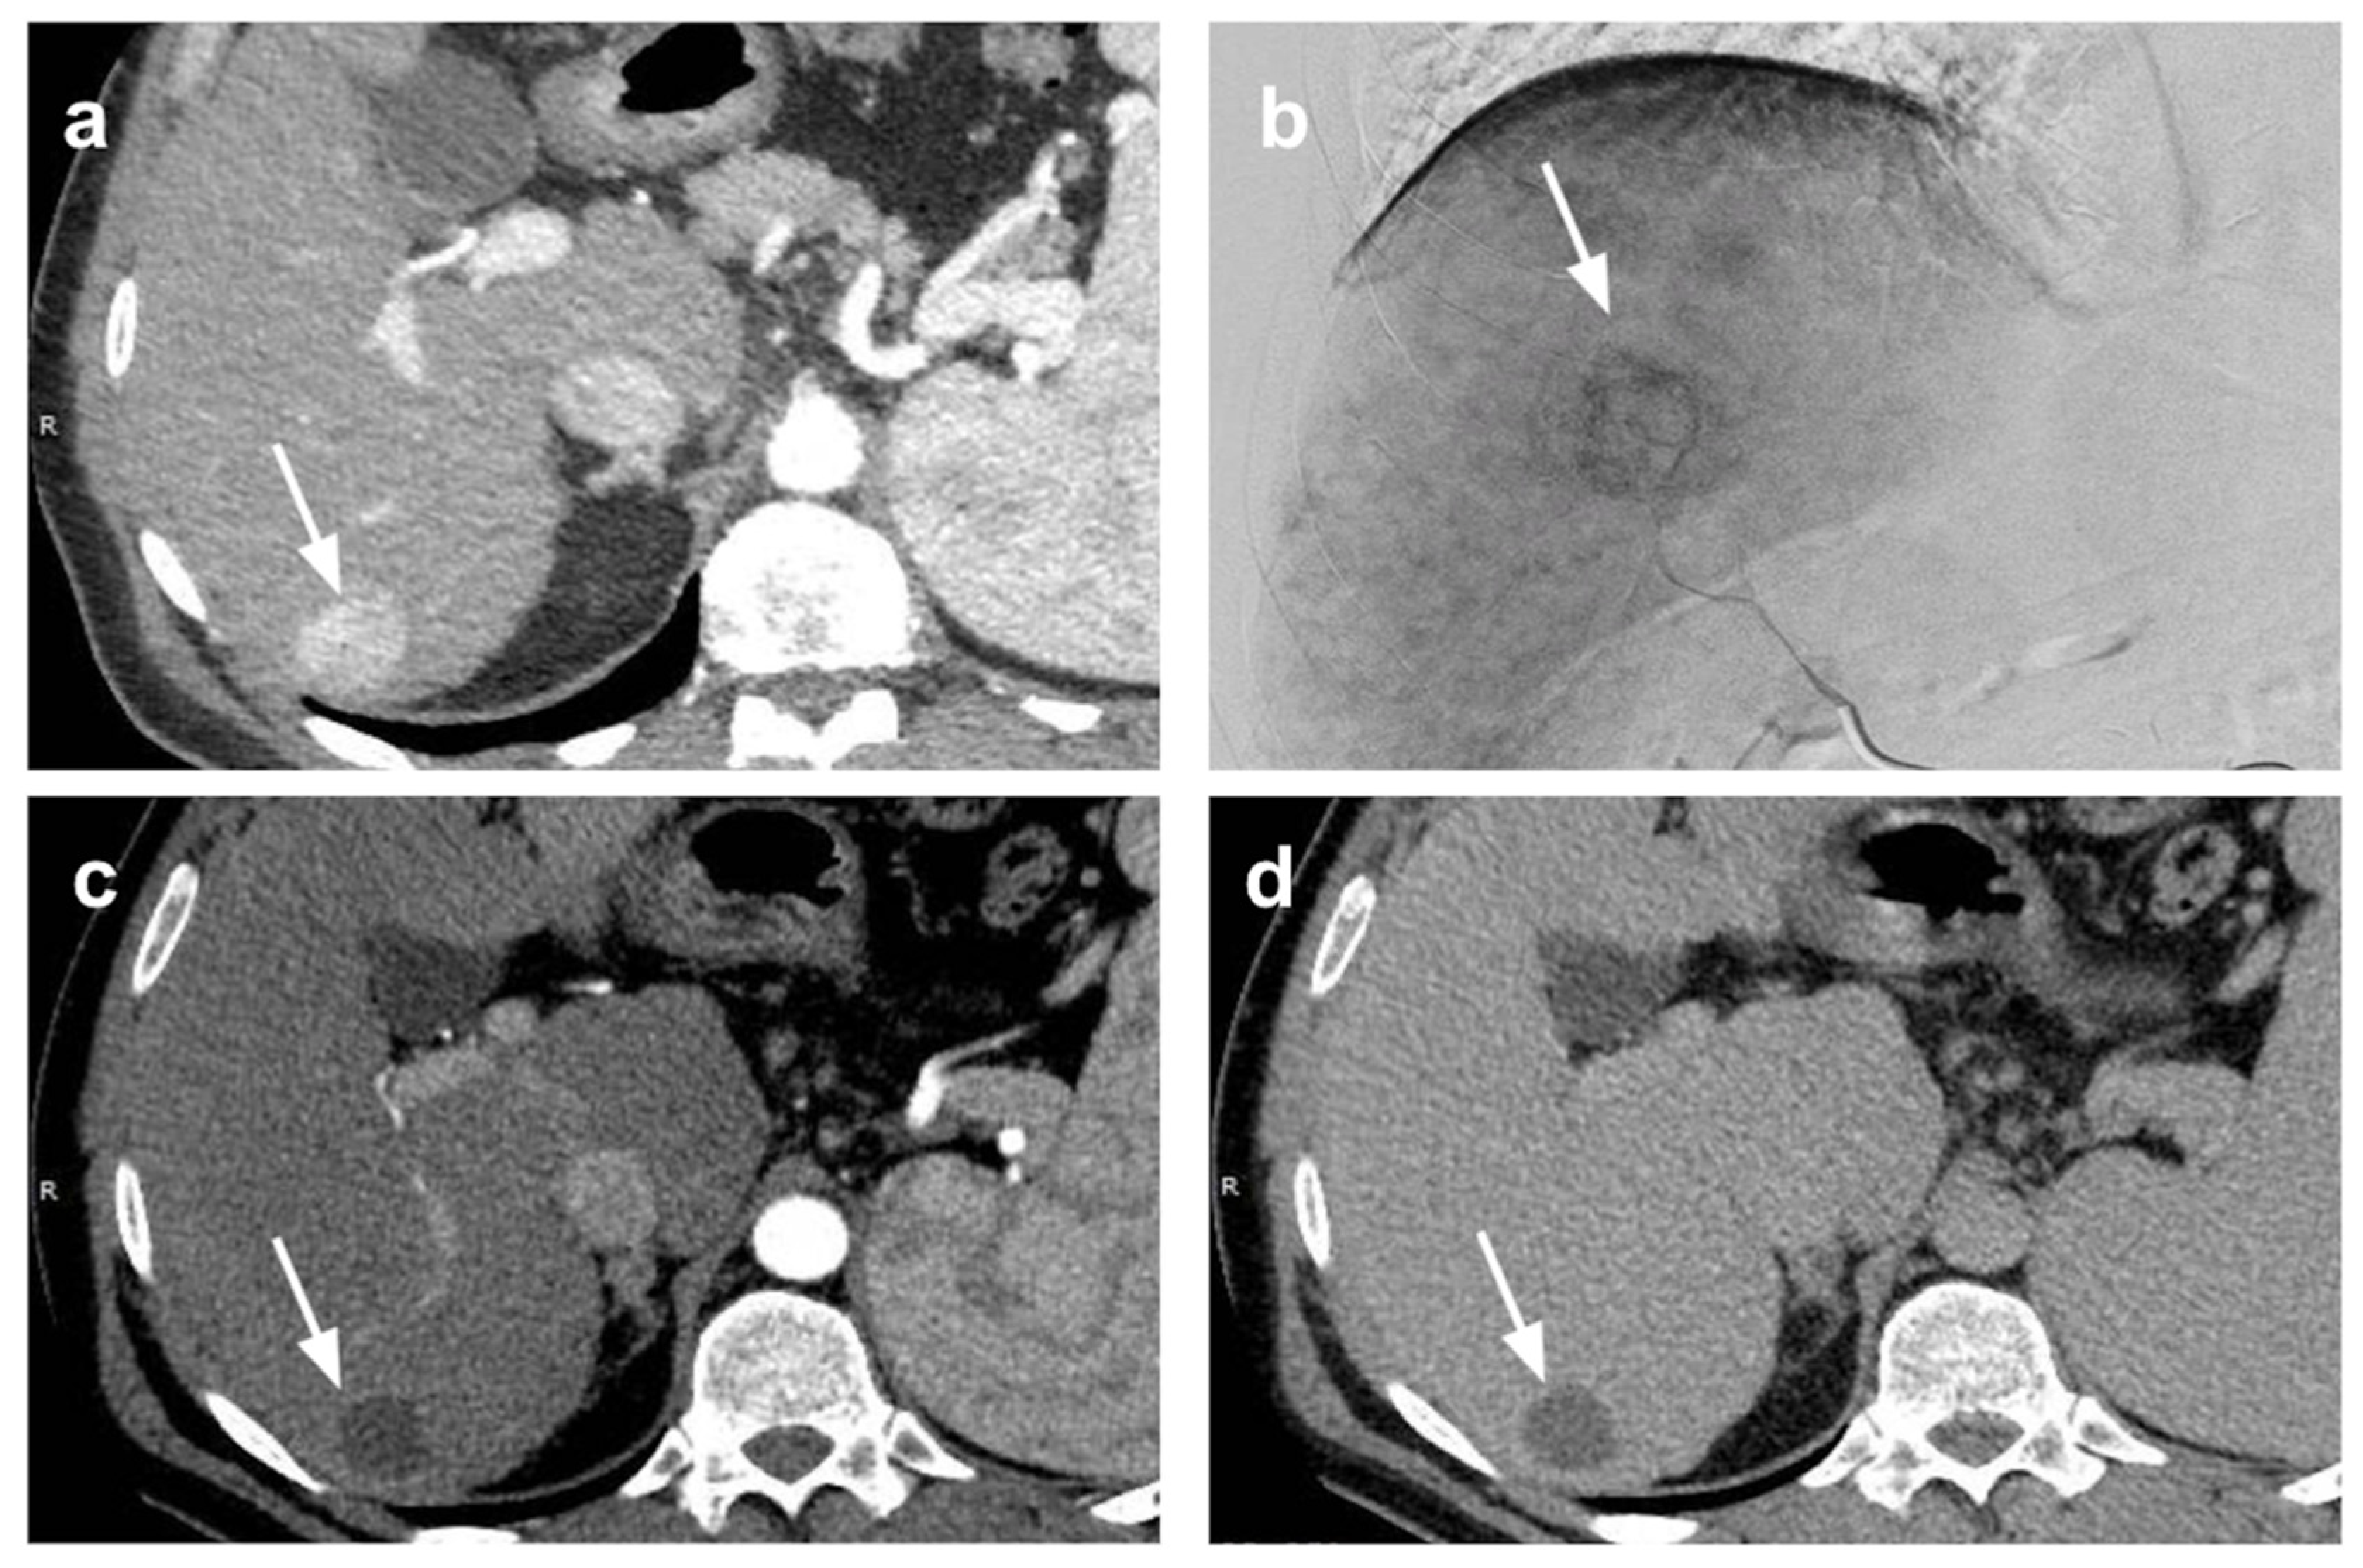

- Ibrahim, S.M.; Kulik, L.; Baker, T.; Ryu, R.K.; Mulcahy, M.F.; Abecassis, M.; Salem, R.; Lewandowski, R.J. Treating and Downstaging Hepatocellular Carcinoma in the Caudate Lobe with Yttrium-90 Radioembolization. Cardiovasc. Intervent. Radiol. 2012, 35, 1094–1101. [Google Scholar] [CrossRef]

- Levi Sandri, G.B.; Ettorre, G.M.; Colasanti, M.; De Werra, E.; Mascianà, G.; Ferraro, D.; Tortorelli, G.; Sciuto, R.; Lucatelli, P.; Pizzi, G.; et al. Hepatocellular Carcinoma with Macrovascular Invasion Treated with Yttrium-90 Radioembolization Prior to Transplantation. Hepatobiliary Surg. Nutr. 2017, 6, 44–48. [Google Scholar] [CrossRef] [PubMed] [Green Version]

- Assalino, M.; Terraz, S.; Grat, M.; Lai, Q.; Vachharajani, N.; Gringeri, E.; Bongini, M.A.; Kulik, L.; Tabrizian, P.; Agopian, V.; et al. Liver Transplantation for Hepatocellular Carcinoma after Successful Treatment of Macrovascular Invasion–A Multi-center Retrospective Cohort Study. Transpl. Int. 2020, 33, 567–575. [Google Scholar] [CrossRef] [PubMed]